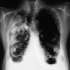

Курение — одна из причин возникновения

бронхита,

рака легких, а также отрицательных изменений во всем организме, особенно у женщин и детей. И неважно, много или мало женщина курит.

Наверняка многие из нас, особенно те, кто является поклонником Александра Абдулова, были потрясены неожиданным известием, что у знаменитого актера обнаружен

рак легкого, причем уже в запущенной четвертой стадии. Удивительным для людей, далеких от медицины, оказалось и то, что болезнь обнаружена не сразу, а после очень тщательного обследования, и окончательный диагноз был поставлен лишь в специализированной израильской клинике.